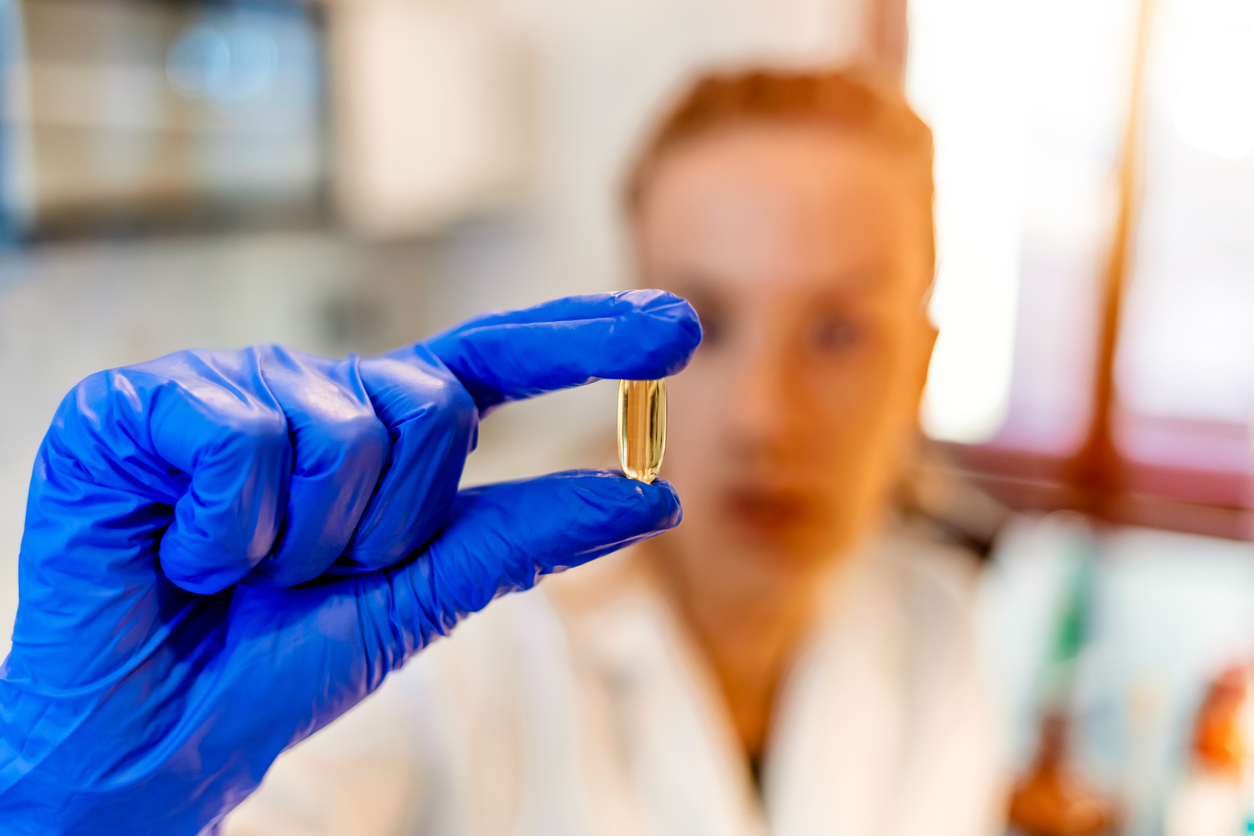

Food sources of vitamin D include fatty fish (salmon, mackerel, sardines, cod liver oil) and some types of mushrooms (Shiitake), especially if sundried, contain cholecalciferol (vitamin D3). Because vitamin D not easily obtained from food, many countries, including the US and Canada, encourage the fortification of commonly consumed foods, such as milk, orange juice, other dairy products and cereals with vitamin D. Many people have inadequate sun exposure to meet vitamin D requirements and few people are able to obtain enough vitamin D from food sources alone, therefore supplementation is important. How much to supplement is less clear and will vary based on vitamin D status. Deficient and insufficient individuals will need a different supplemental strategy than those who are not. There is no agreed upon dose globally, recommendations often range from 400-2000 IU (10-50 mcg)/day and your doctor may recommend more. However, a common dose of 1000 IU (25 mcg) of vitamin D3, has been identified to be safe and beneficial for health. 22